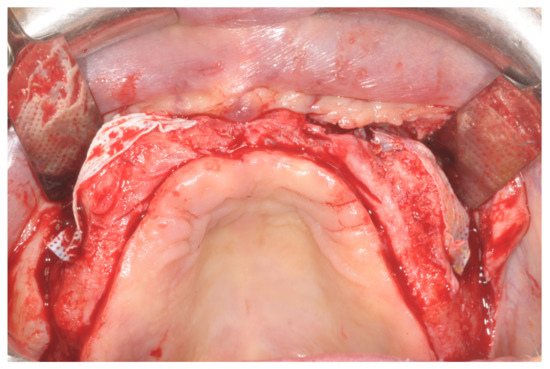

Patients rinsed with a chlorhexidine mouthwash (0.2%) for 1 min immediately prior to the intervention. Local anesthesia were administered using mepivacaine with adrenaline at ratios of 1:100,000 or 1:50,000. Crestal incisions were made with releasing incisions far away from the future membrane positioning and full thickness flaps were elevated. After the meticulous removal of all residual soft tissues in the regenerating site, copious bleeding was induced using a bone scraper (Safescraper Curve TWIST, META, Reggio Emilia, Italy) (Figure 1). A prosthetically guided implant placement was performed following the instructions of manufacturer (Thommen Medical, Grenchen, Switzerland). Only 1 patient had implants placed 9 months after bone augmentation because the initial bone thickness did not permit the primary stabilization of the implant fixtures (Figure 2, Figure 3, Figure 4, Figure 5, Figure 6, Figure 7 and Figure 8).

Figure 1. Graft recipient area after bone decorticalization and distal fixation of the non-resorbable barrier.